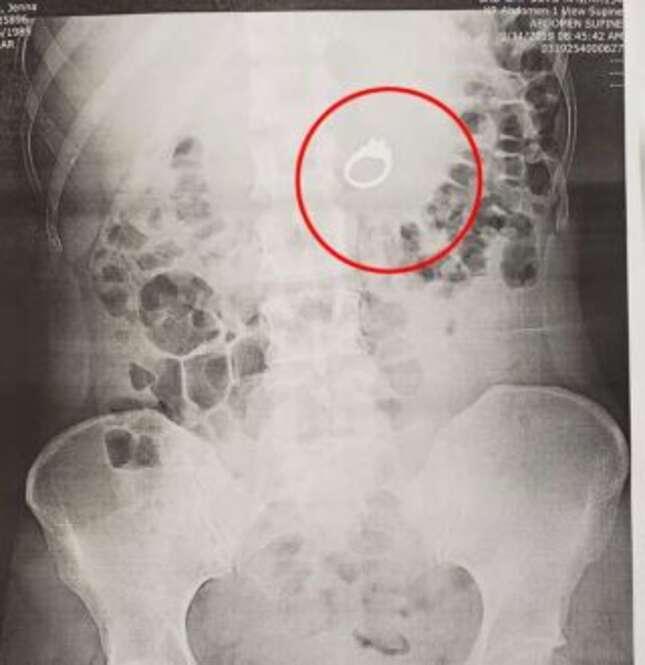

Horas después, su prometido y ella acudieron a urgencias donde tuvieron que explicar a varios médicos lo que había sucedido: “El médico ordenó una radiografía y parecía bastante sorprendido cuando regresó con un segundo médico y me mostró que, efectivamente, ¡mi anillo estaba justo en mi estómago! Definitivamente podía sentirlo en mis entrañas, estaba empezando a doler mucho y nos ponía nerviosos”.